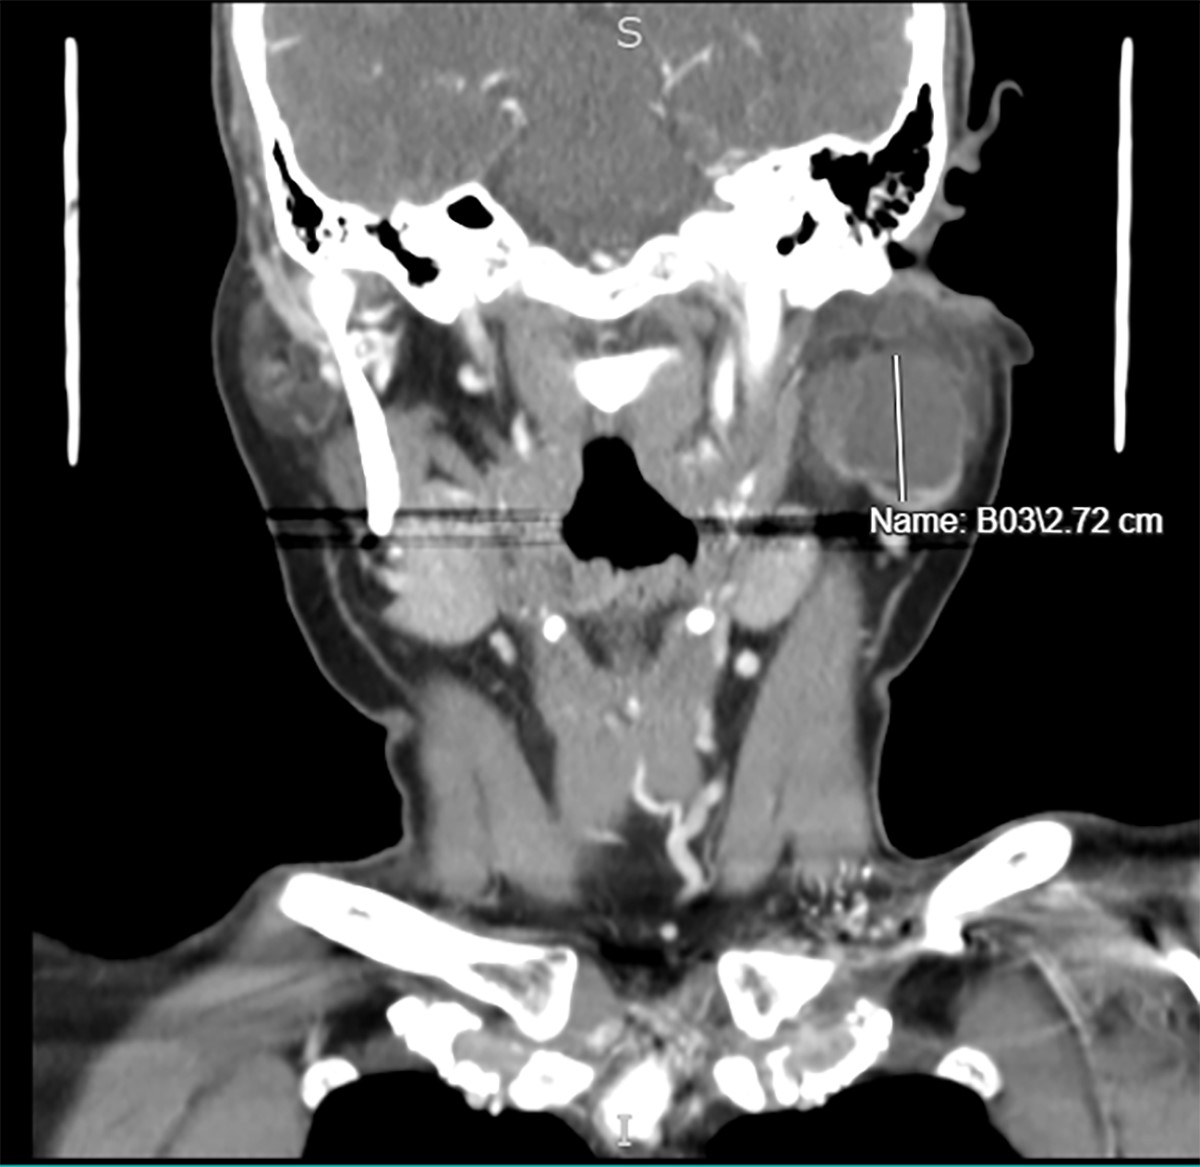

- Well defined, thin, smooth walled unilocular cystic mass (Int J Surg Case Rep 2017;41:383)

Radiology images